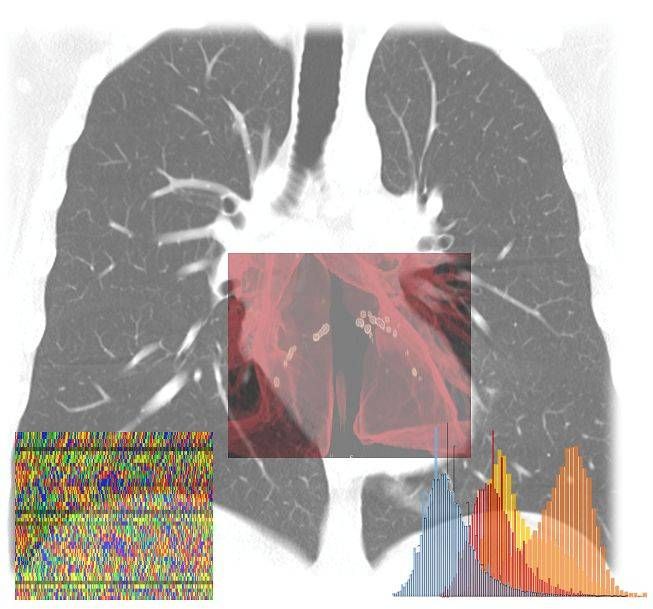

Il progetto partirà da questo secondo obiettivo, con un algoritmo AI che integrerà immagini diagnostiche, parametri clinici e di laboratorio, stato infiammatorio, e profilo genetico del paziente e del virus.